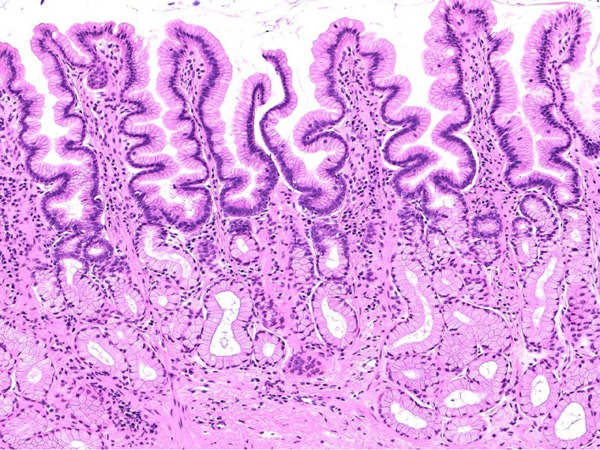

頻繁に嘔吐・下痢をするワンちゃんの精密検査依頼で内視鏡検査のご紹介がありました。内視鏡検査で上部・下部消化管を検査し、粘膜を採取し病理組織検査に出しました。結果は「胃:らせん菌感染を伴う慢性胃炎(中程度)/結腸:慢性腸炎(軽度)」とのことでした。その後かかりつけの先生のところでの治療となりました。